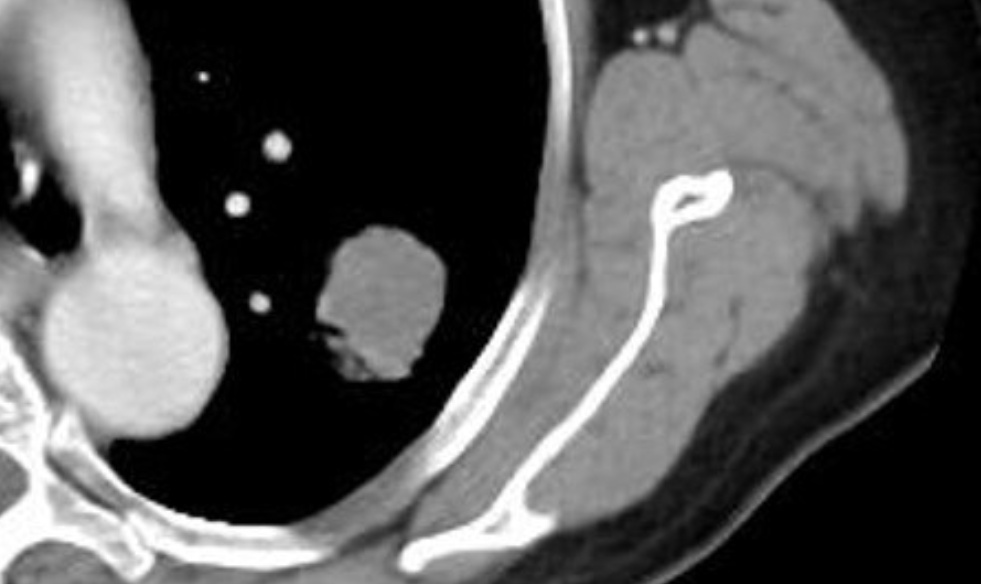

平扫CT纵隔窗密度约40HU

PET-CT显示病灶糖代谢摄取高,

诊断为恶性肿瘤